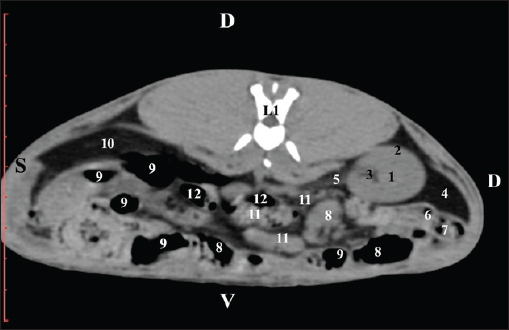

At the next scan level (L1), the normoattenuated image of the right kidney was more detailed and in contact with the lobus hepatis dexter, lobus caudatus, duodenal pars descendens, and ileum. The cortex renis and medulla renis were not clearly differentiated. Pelvis renalis appeared as a linear hypoattenuated finding against the relatively normoattenuated kidney cortex and medulla. The proximal part of the ureter was seen medial to the right kidney (Figs. 2 and 3).

Fig. 2. Pre-contrast computed tomography (CT) anatomical scan of the regio abdominis cranialis at the L1 level. (1) Ren dexter; (2) lobus hepatis dexter; (3) lobus caudatus (proc. caudatus) with visceral adipose tissue; (4) pars descendens of the duodenum; (5) ileum; (6) cecum; (7) colon ascendens; (8) colon transversum; (9) colon descendens; (10) jejunum.

Fig. 3. Pre-contrast computed tomography (CT) anatomical scan of regio abdominis cranialis at the L1 level. (1) Medulla renis; (2) cortex renis; (3) pelvis renalis; (4) lobus caudatus (proc. caudatus) with visceral adipose tissue; (5) ureter; (6) pars descendens of the duodenum; (7) jejunum; (8) cecum; (9) colon ascendens; (10) lien; (11) colon descendens; (12) colon transversum.